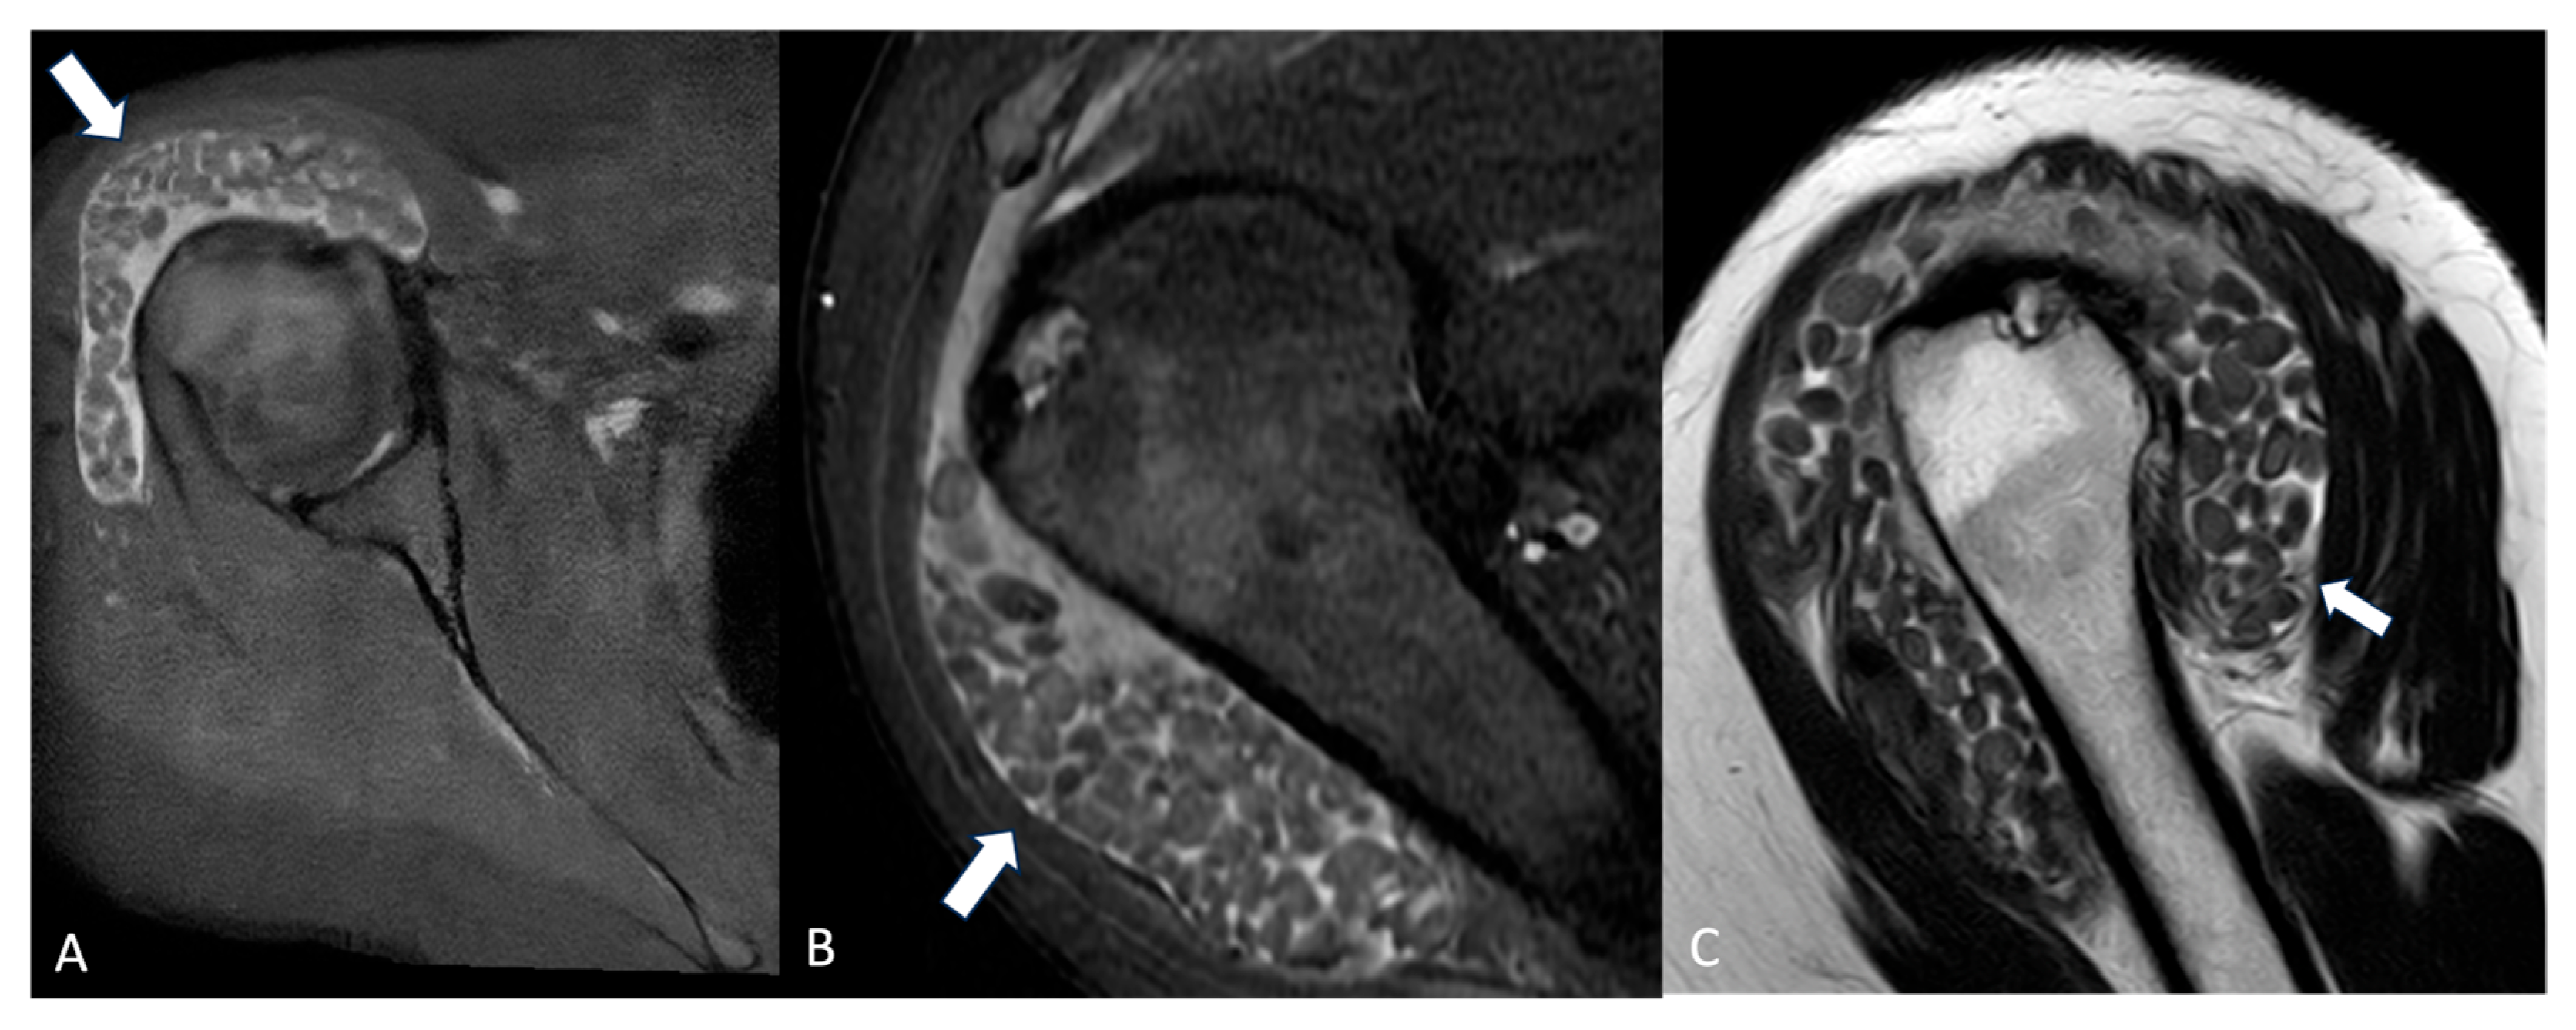

Synovial chondromatosis (Figure 3) may develop as a complication of chronic bursitis [24].

Figure 3.

Axial PD-FS (A), coronal PD-FS (B), and T2-weighted (C) MRI images of a 48-year-old female patient presenting with shoulder pain and swelling. Multiple non-osseous cartilaginous loose bodies (arrows) are visible within the bursa, which appears enlarged, causing bulging of the deltoid muscle. Findings are consistent with synovial chondromatosis.